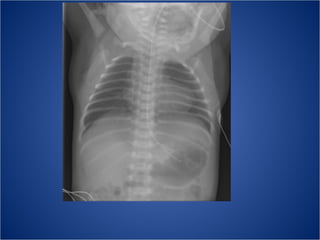

ToF Pulmonalisklep stenose Rechter ventrikel hypertrofie VSD Overriding aorta De RV hypertrofie veroorzaakt dat de hartpunt opwipt > het zgn schoenhart

ToF Cyanostische congenitale hartafw > het bloed stroomt direct vanuit de re kamer naar de ao via het VSD > niet gesatureerd bloed komt in de circulatie Extreem: pulmonalis atresie X-thorax 20% rechtsdesc. Ao Opvallend weinig longvaattekening (kan heel asymm zijn) Normale hartgrootte Rel. grote aoboog Kleine hili

ToF Pulmonalisklep stenoseRechter ventrikel hypertrofie VSD Overriding aorta De RV hypertrofie veroorzaakt dat de hartpunt opwipt > het zgn schoenhart

ToF Cyanostische congenitalehartafw > het bloed stroomt direct vanuit de re kamer naar de ao via het VSD > niet gesatureerd bloed komt in de circulatie Extreem: pulmonalis atresie X-thorax 20% rechtsdesc. Ao Opvallend weinig longvaattekening (kan heel asymm zijn) Normale hartgrootte Rel. grote aoboog Kleine hili